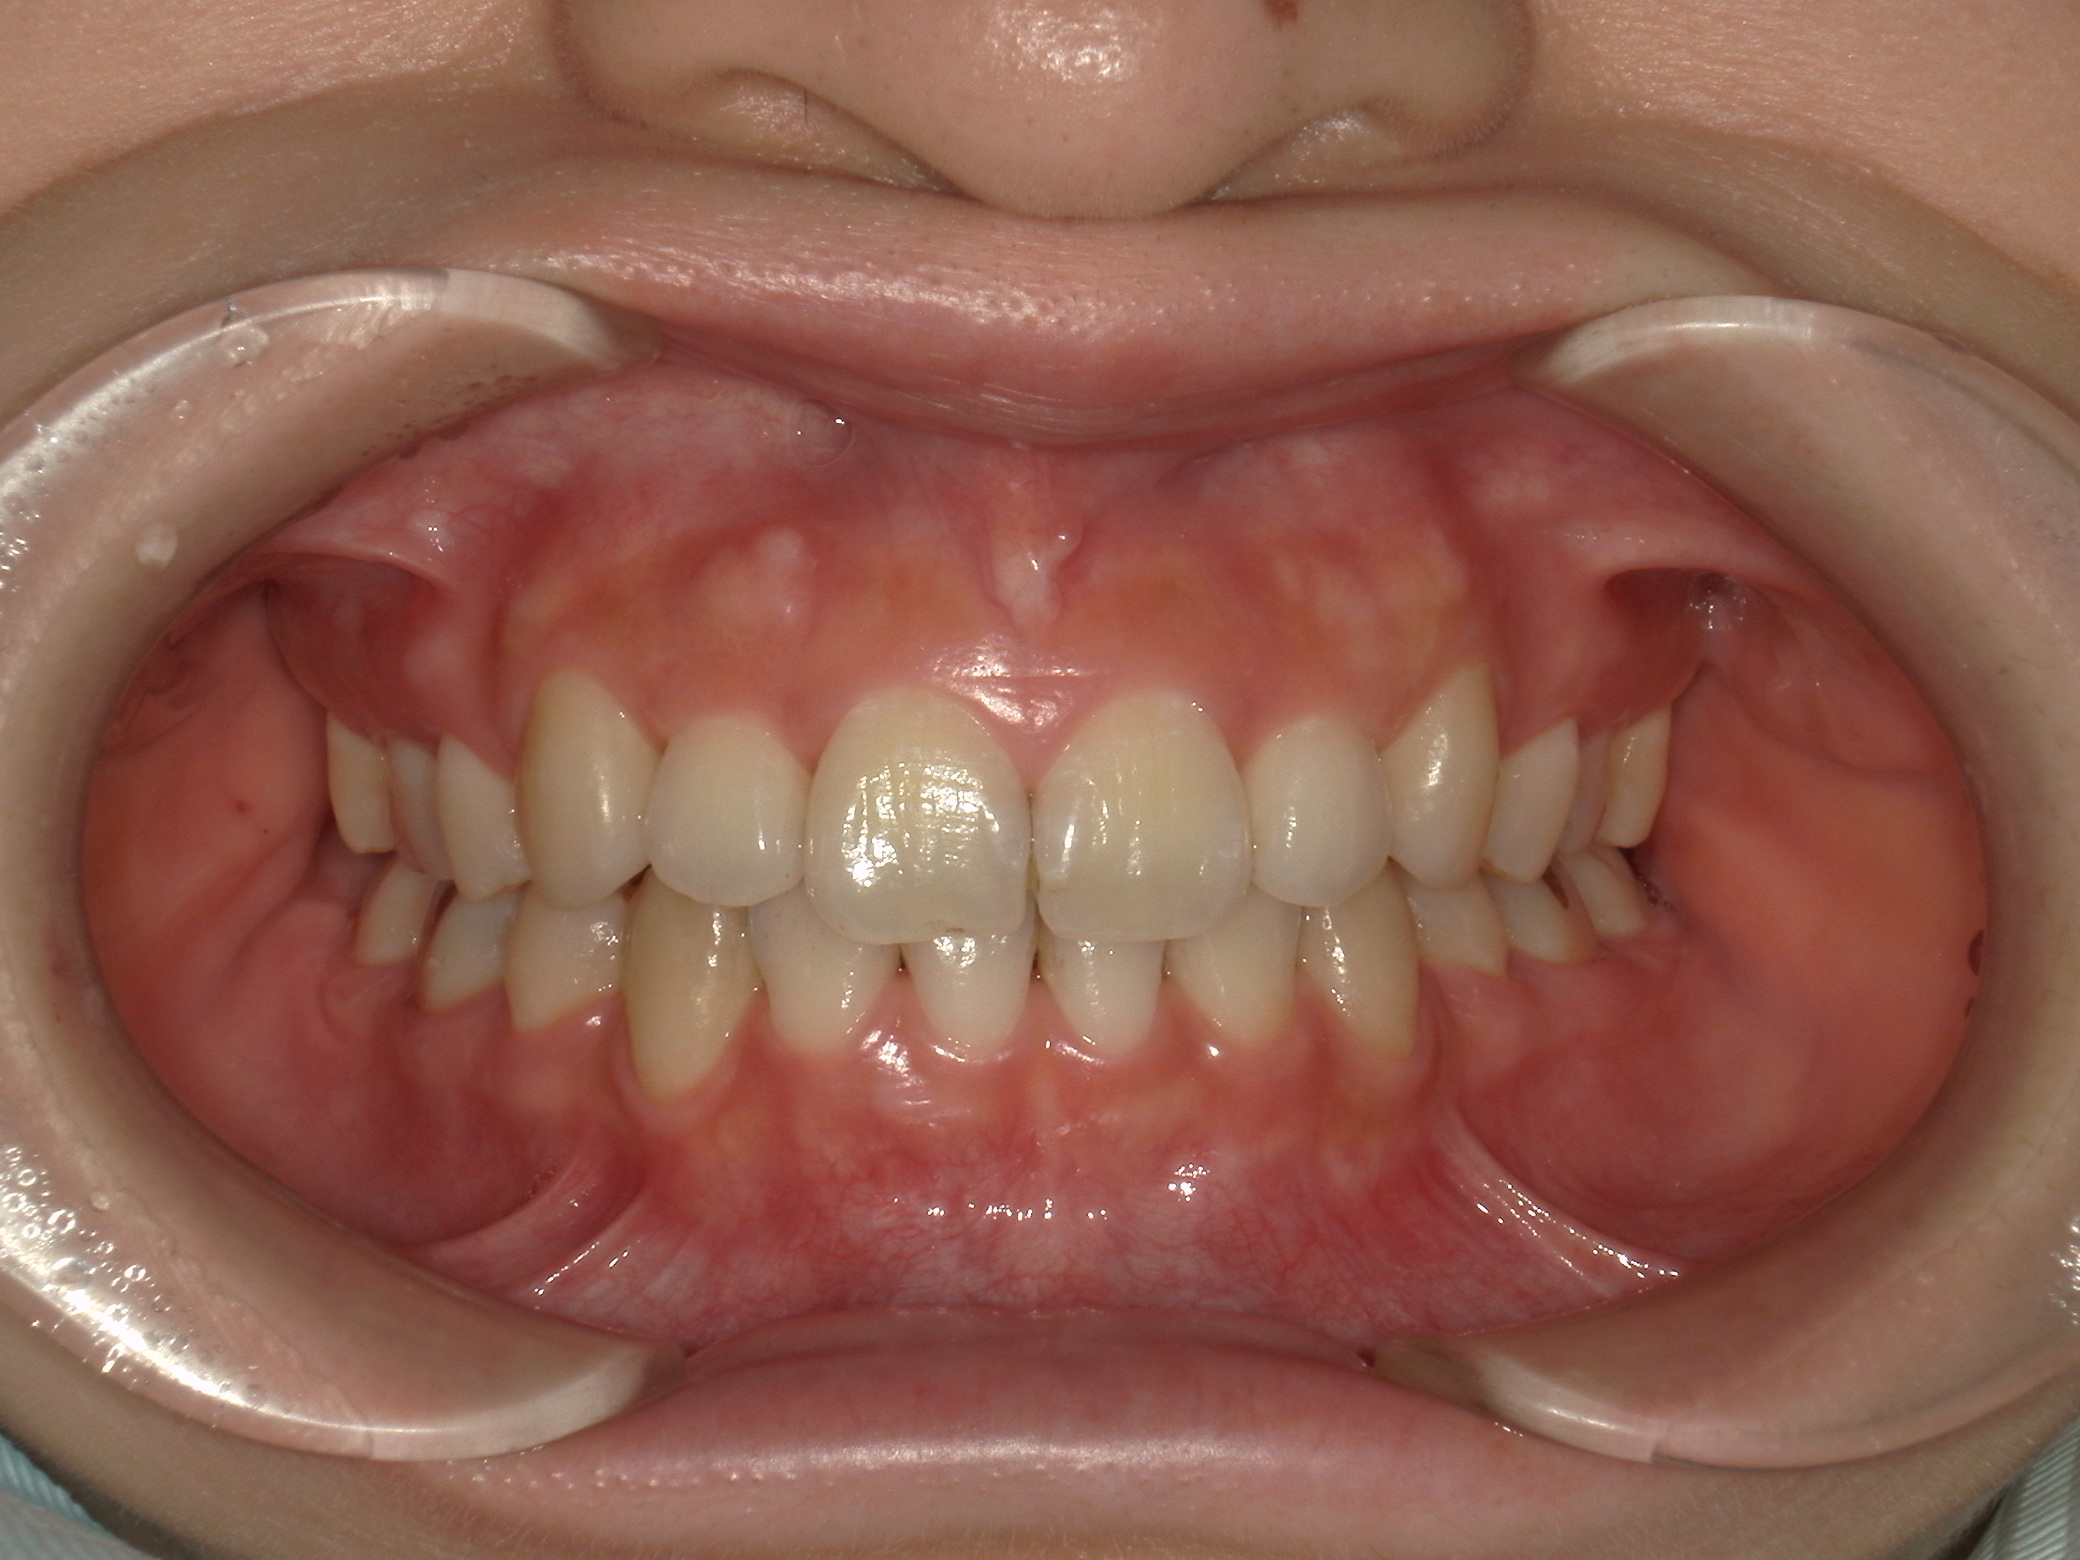

上下顎に叢生(歯並びのガタガタ) と部分的な反対咬合を認める。

本症例は上下小臼歯抜歯により叢生解消のスペースを獲得し、下顎位の後退があることからダイレクトスプリント治療を併用して顎位の安定を求めた。